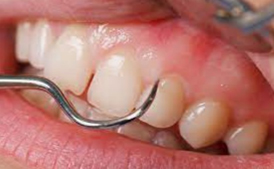

歯石が多く沈着し歯周病が進行している状態

実際の治療としては、まず歯面のプラークおよび歯石の付着状況・歯周ポケットの深さ・歯肉からの出血の有無・歯の動揺度を検査、測定し、歯肉炎および歯周炎に罹患しているかどうかを確認します。

検査にて歯肉炎・歯周炎と診断された場合は、スケーラーと呼ばれる専門の器具を用いて、プラークおよび歯石除去を行います。状態によっては痛みを伴う場合がありますので、必要に応じて麻酔を行う場合があります。